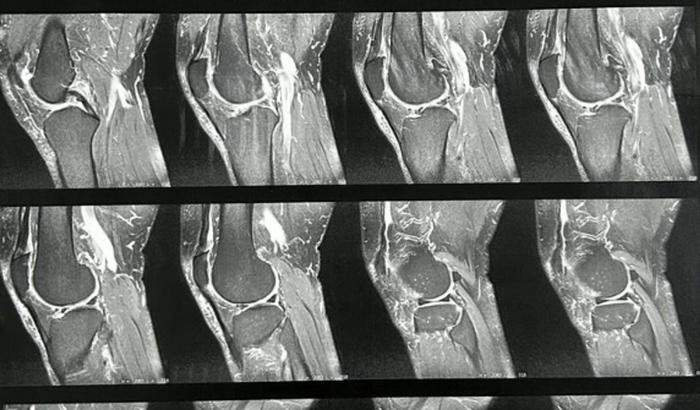

Meu nome é Octaviano Diniz, tenho 67 anos e estou enfrentando um desafio significativo em minha vida. O desgaste nos meus joelhos tem impactado minha capacidade de locomoção, e a perspectiva de perder a habilidade de andar é assustadora.

Recebi a recomendação médica de um tratamento com aplicação de ácido hialurônico (viscossuplementação) a cada 3 meses, no valor de R$3000,00 a cada trimestre. Além disso, o suporte adicional de um fisioterapeuta é essencial para fortalecer meus joelhos. Este tratamento tem um custo mensal de R$900,00.